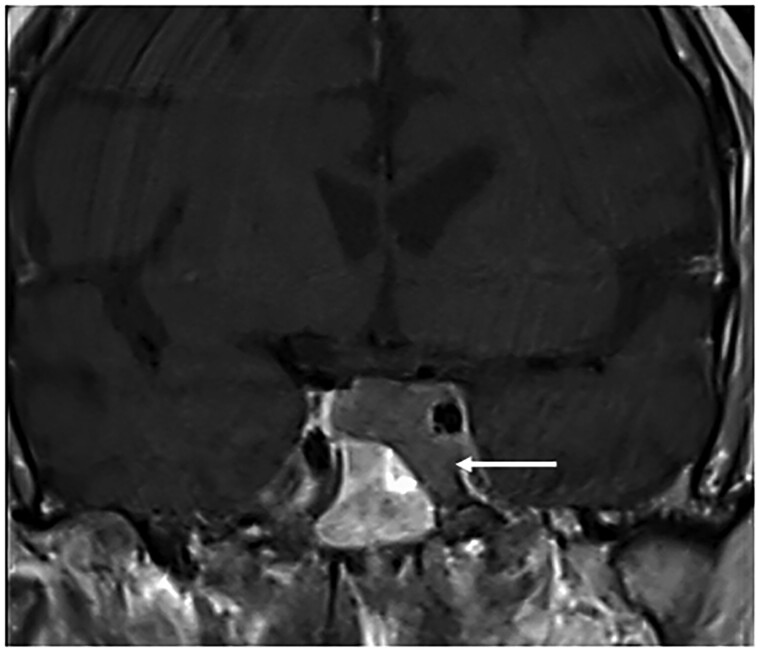

库欣综合征(CS)是由于长期暴露于过量的糖皮质激素,导致一系列临床表现,包括无血管坏死(AVN),一种罕见的CS并发症。虽然AVN通常与外源性糖皮质激素治疗有关,但它也可能发生在内源性CS中,但由于其罕见性和可能的亚临床表现而未被识别。我们描述了一例71岁的男性库欣病患者,他最初表现为双侧髋关节AVN,后来发展为双侧肩部AVN,尽管经蝶窦手术和辅助立体定向光子放射治疗后生化缓解。内源性CS中AVN的报道不足,缺乏常规筛查的指导。我们的病例强调了在CS患者中考虑AVN的重要性,特别是那些持续或反复出现关节症状且皮质醇水平明显升高的患者。早期发现AVN是至关重要的,因为如果不治疗,它可能导致不可逆转的关节损伤和残疾。应探索筛查策略,识别诊断为CS的高危患者,及时干预,从而预防AVN相关的长期发病。

Cushing syndrome (CS) results from prolonged exposure to excess glucocorticoids, leading to a range of clinical manifestations including avascular necrosis (AVN), a rare complication of CS. Although AVN is often associated with exogenous glucocorticoid treatment, it can occur in endogenous CS but may be unrecognized because of its rarity and possibly from a subclinical presentation. We describe a case of a 71-year-old male with florid Cushing disease who initially presented with bilateral hip AVN and later developed bilateral shoulder AVN despite achieving biochemical remission following transsphenoidal surgery and adjuvant stereotactic photon radiosurgery. AVN in endogenous CS is underreported, and guidance on routine screening is lacking. Our case underscores the importance of considering AVN in patients with CS, especially in those with persistent or recurrent joint symptoms and markedly elevated cortisol levels. Early detection of AVN is crucial as it can lead to irreversible joint damage and disability if untreated. Screening strategies should be explored to identify high-risk patients who are diagnosed with CS for timely intervention, thereby preventing long-term morbidity associated with AVN.